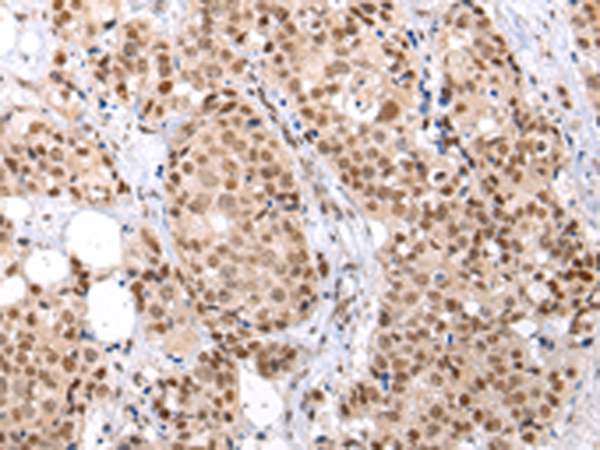

分类: 科研抗体货号: P12486别名: CDX3; CDX-3; CDX2/AS应用: WB,IHC反应种属: Human, Mouse